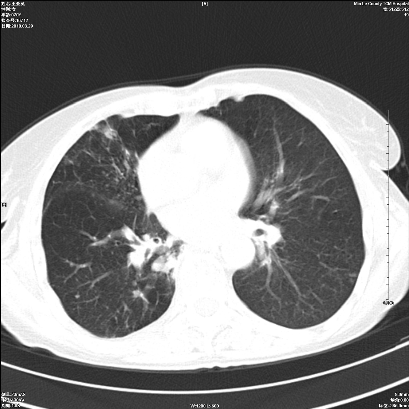

右肺上叶支气管开口阻塞,上叶呈不均匀致密影,右肺中下叶内见斑片状密度增高影,上叶见钙化点,纵隔内见钙化淋巴结,桶状胸,右下肺动脉增粗,残根征,意见:1.右肺中心性肺癌;2.右肺陈旧性结核;3.肺心病。

ct所见:右肺上叶肺不张,呈软组织密度影向肺门区聚拢,其内可见含气段支气管及细支气管影,病灶内尚可见钙化结节。右肺上叶支气管狭窄,段支气管壁可见钙化。右肺下叶背段、右肺中叶见不规则小片絮状影及纤维条索影,形态较僵硬。右肺中叶胸膜旁可见多个小结节影。纵膈内见钙化淋巴结。

分析:右侧胸廓及右肺体积缩小,说明病变时间比较长了,应该是有数年的时间了,如果是短期内出现的肺不张,只会引起纵膈向患侧移位,而不会引起胸廓的塌陷。不张的肺组织内可见含气支气管影,说明右肺上叶支气管没有完全中断,只是狭窄。右肺中叶、下叶散在不规则病灶,部分呈纤维化改变。纵膈内的淋巴结大部分钙化。因此,本例给我的感觉良性病变的可能是大。

结论:考虑右肺上叶支气管内膜结核合并右肺上叶肺不张;右肺中叶、下叶陈旧性肺结核改变。